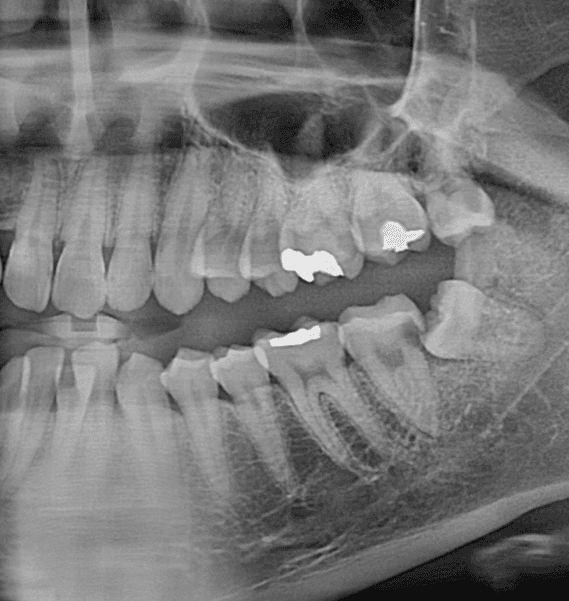

이정도로 상한 치아는 임플란트 해야되나요?

왼쪽 아래 사랑니가 맨 끝 어금니에 충치를 전이시킨 상태라고 하는데요 발치 후 임플란트를 추천하시더라구요

엑스레이상으로 봤을때 임플란트 할 정도로 심각한 상태인건가요?

• 사랑니로 인해서 앞치에 충치가 많이 생긴 것으로 보입니다. 하지만 앞의 치아에 뿌리는 건강하게 잘 남아 있기 때문에 발치를 한다기보다도 치료를 해서 사용하는 것이 좋습니다. 자세한 확인을 위해서 치과에서 진료를 받아보는 것을 권유드립니다

충치가 깊어 신경치료 및 크라운이 필요한 상황입니다. 발치 후 임플란트 시도하기 전에 치아를 보존해보기를 원하신다면 치과대학병원 치과보존과에 내원하여 상담받아 보세요.

다만 충치자체 양상을 보면 신경치료 후 크라운씌워 살릴 수 있을정도입니다 바로 발치를 해야하는 상황은 아닐것 같습니다

• 사진이 파노라마라서 명확한 진단은 어렵습니다만 굳이 바로 빼기보다는 신경치료 및 크라운 치료를 통해서 한번 살려볼 수 있어보입니다.